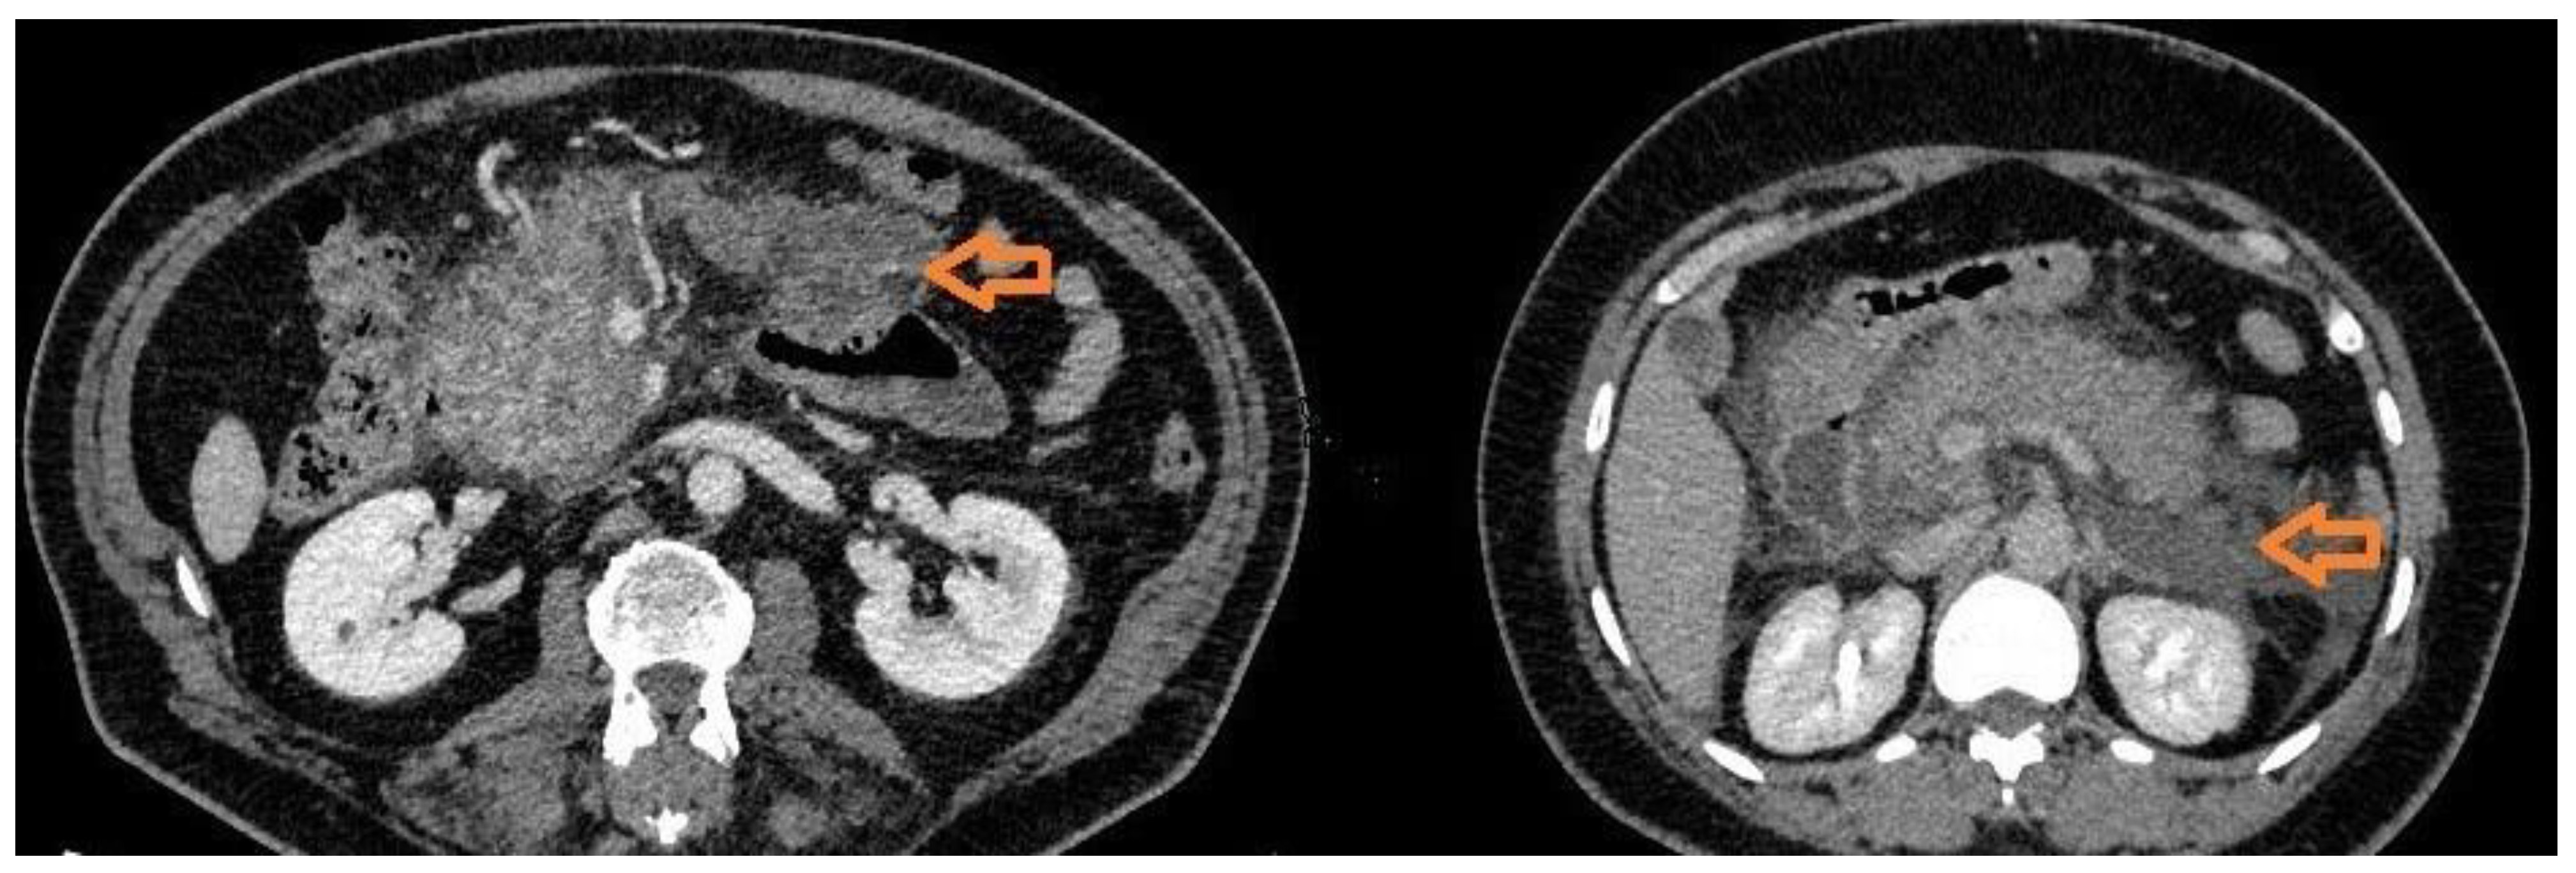

Figure 1. CT appearance of acute pancreatitis. The image on the left depicts a case of necrotising pancreatitis. The pancreas is markedly enlarged with peripancreatic walled off necrosis at initial stage, characterized by an irregular and heterogeneous appearance, irregular wall, with a mild enhancement and non-solid content (arrow). The image on the right depicts a case of acute oedematous pancreatitis. The gland in enlarged with homogenous enhancement and a fluid peripancreatic effusion (arrow).